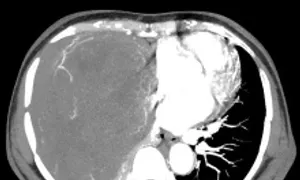

Bệnh nhân cho biết lý do không phẫu thuật khi ấy bởi u nhỏ không gây khó chịu. Gần đây bà khó thở, sức khỏe giảm sút, sụt 5 kg. Bác sĩ Bệnh viện Ung bướu Hà Nội khám ghi nhận lồng ngực phải bệnh nhân có khối đặc kích thước 20x15 cm đè xẹp phổi, thâm nhiễm trung thất, thành ngực. Sinh thiết khối u kết quả giải phẫu bệnh là u xơ đơn độc.

Bác sĩ tiên lượng ca mổ lấy u nhiều khó khăn do bệnh nhân có thể trạng gầy yếu, khối u lớn giàu mạch nuôi chiếm gần hết khoang lồng ngực. Ngày 30/9, TS.BS. Phan Lê Thắng, Trưởng khoa Ngoại Theo yêu cầu, Bệnh viện Ung Bướu Hà Nội, cho biết êkíp phẫu thuật hội chẩn tính toán kỹ phương án mổ, khống chế nguồn mạch máu nuôi để hạn chế mất máu cho bệnh nhân. Khối u được bóc tách thành công, nặng hơn 2 kg.

Hình ảnh khối u choán hết khoang lồng ngực của bệnh nhân. Ảnh: Bệnh viện cung cấp